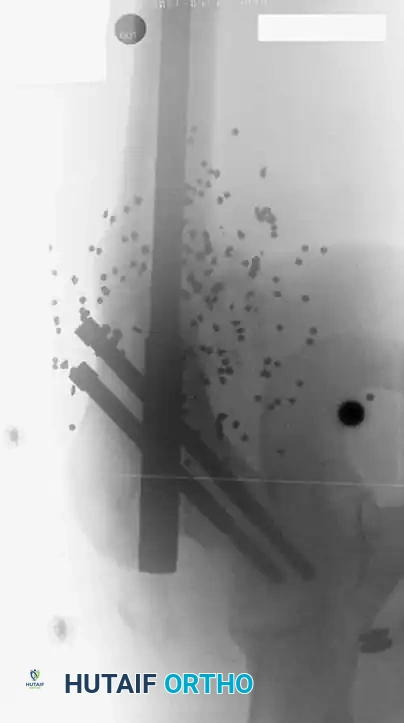

SURGICAL TECHNIQUE: DAMAGE CONTROL EXTERNAL FIXATION

When a polytrauma patient is deemed too unstable for definitive fixation (e.g., severe acidosis, hypothermia, coagulopathy), Damage Control Orthopaedics via rapid external fixation is indicated.

2. Pin Placement and Safe Corridors

• Femur: Half-pins (5.0 mm or 6.0 mm) are placed laterally or anterolaterally. Avoid the medial neurovascular bundle. Ensure pins are placed far enough from the fracture site to avoid contaminating the future zone of intramedullary nailing.

• Tibia: Pins are placed on the anteromedial face of the tibia (subcutaneous border).

• Technique: Make a generous stab incision. Use blunt dissection down to the bone to protect cutaneous nerves and veins. Use a drill sleeve. Pre-drill both cortices with a sharp drill bit to prevent thermal necrosis, which is the leading cause of pin-tract infection and loosening. Insert the Schanz pins bicortically.

3. Frame Construction and Reduction

• Apply bar-to-pin clamps and connect them with carbon fiber or radiolucent rods.

• Apply longitudinal traction to restore length, correct rotation, and align the mechanical axis.

• Tighten the clamps sequentially. A delta frame or multi-planar construct can be utilized if additional stiffness is required.